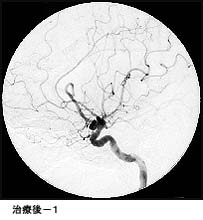

(1)破裂脳動脈瘤に対するGDC(コイル)塞栓術

*術後 コイルにより動脈瘤が写らなくなりました。